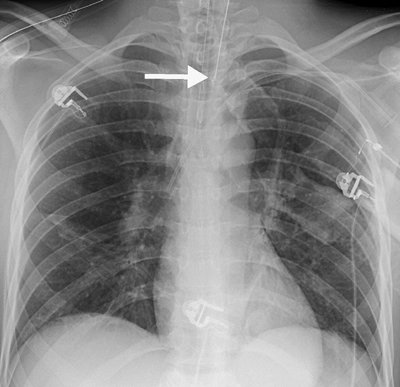

none should be present during diastole. If the catheter is short, dislodgment may occur, and the catheter may enter the right atrium, pulmonary artery, SVC, or coronary sinus. If the lead is too long, a bend in the wire may occur, causing lead fracture (Fig. 5-22). A redundant lead may also perforate the myocardium; this complication generally occurs at the time of or within a few days after insertion. The frontal or lateral radiograph will show the catheter tip outside or within 3 mm of the edge of the cardiac silhouette (Fig. 5-23). Perforation can lead to cardiac tamponade or postcardiotomy syndrome. Inflammation and infection can occur within the vein or the generator pocket; the latter occurs in up to 5% of patients (20). Major vein thrombosis and pulmonary embolism are additional complications of pacemaker insertion.

FIGURE 5-23. Displacement of pacer lead. A: PA chest radiograph shows that the tip of the pacer lead (arrow) is beyond the expected right ventricular wall. B: CT shows the lead outside of the myocardium (arrow). A more inferior image (not shown) showed that the lead tip was within the anterior chest wall.